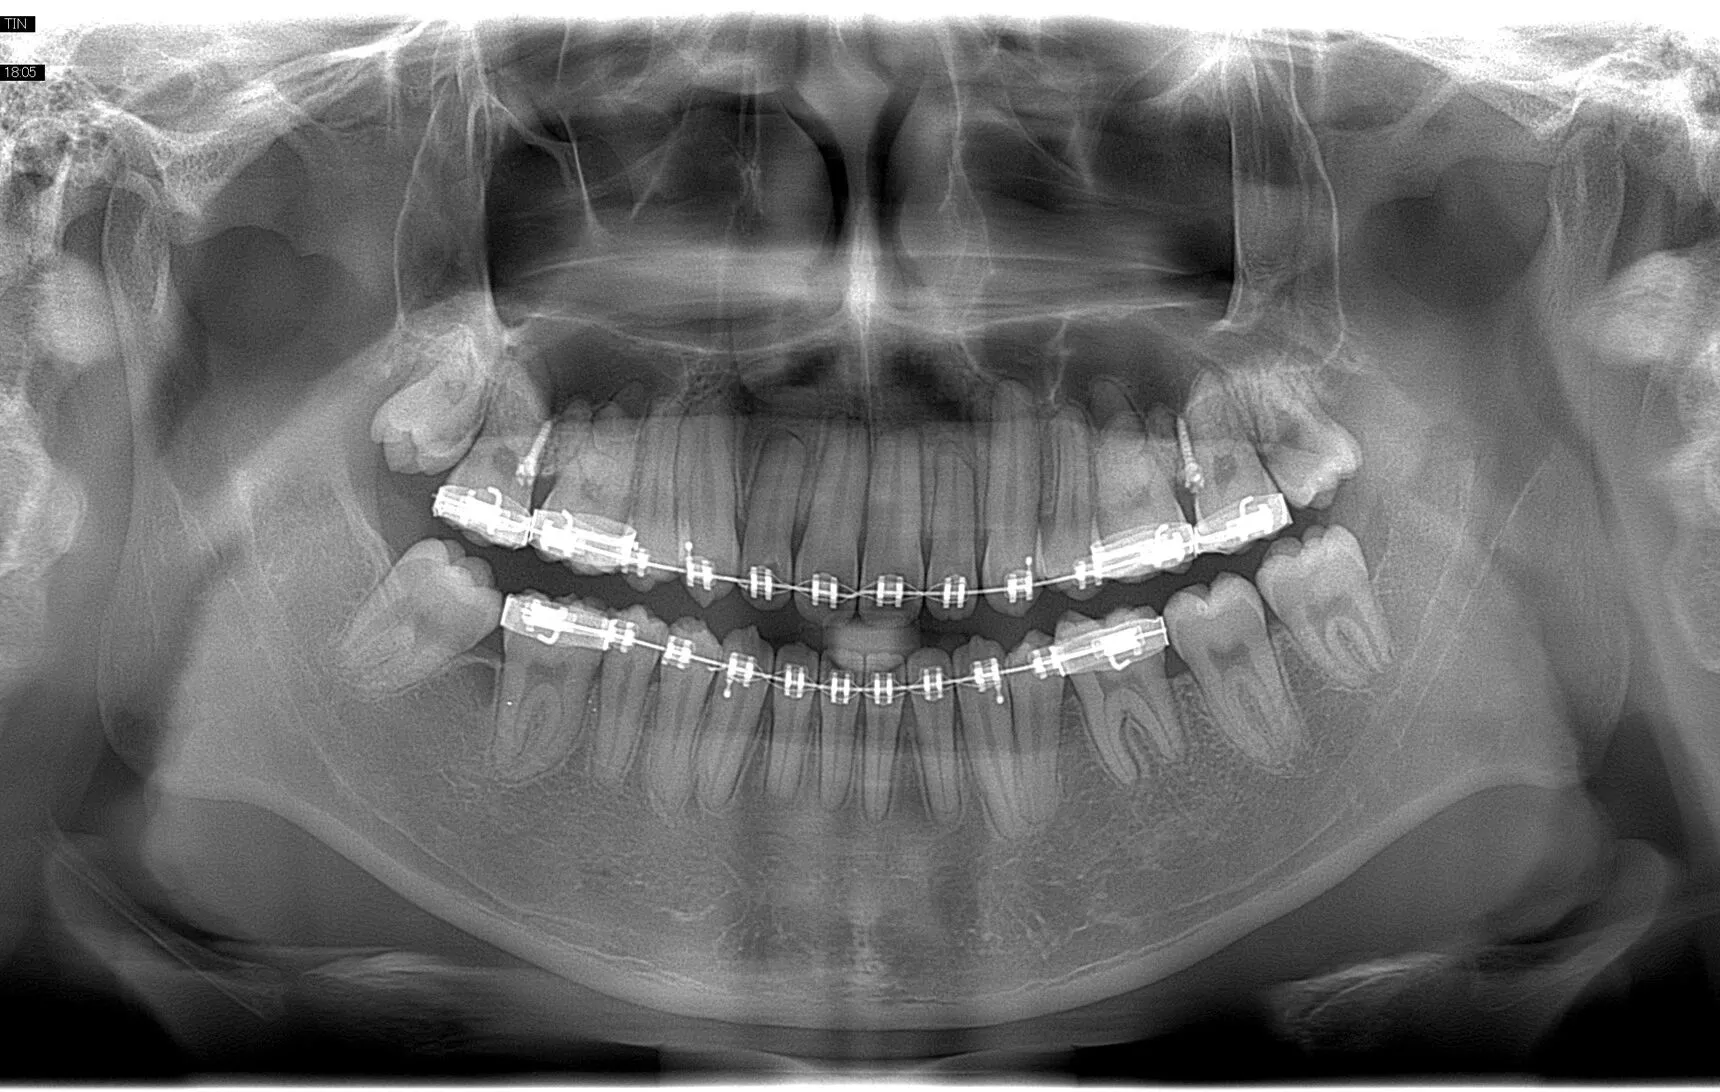

Chất lượng hình ảnh

Công nghệ chụp tự động kỹ thuật số đặc biệt áp dụng tự điều chỉnh thang xám nhằm hạn chế tối đa sai sót, khiến chất lượng hình ảnh cực kỳ rõ ràng và sắc nét.

Các thông số kỹ thuật và cả thời gian chụp đều có thể được lập trình sao cho phù hợp với nhiều kỹ thuật chụp khác nhau, phục vụ đa dạng các trường hợp người bệnh tới khám.